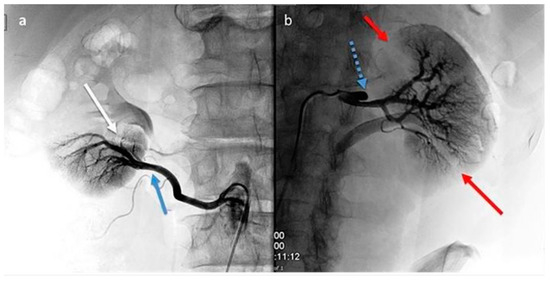

Aiming for a vessel disease diagnosis, computed arteriography with selective renal and polar artery catheterization [2] was performed as a second-level instrumental exam.

This yielded many findings: On the right side, there was an occlusion of a small intraparenchymal terminal branch of the right renal artery, while the inferior polar artery on the right remained patent. On the left side, a dissection of the middle third of the renal artery was observed, characterized by a false occluded lumen and a patent lumen supplying the intrarenal branches; the lower renal polar artery on the left side was also patent (Figure 2a,b).

Figure 2.

(a,b): Digital subtraction angiography (DSA). Right kidney (a): segmental renal artery occlusion (white arrow) consequent to distal dissection (blue arrows) of the inferior polar artery originating from the abdominal aorta. Left kidney (b): renal artery dissection (blue arrow with dots) with occlusion of smaller superior and inferior segmental branches and their corresponding focal de-vascularized areas (red arrows).